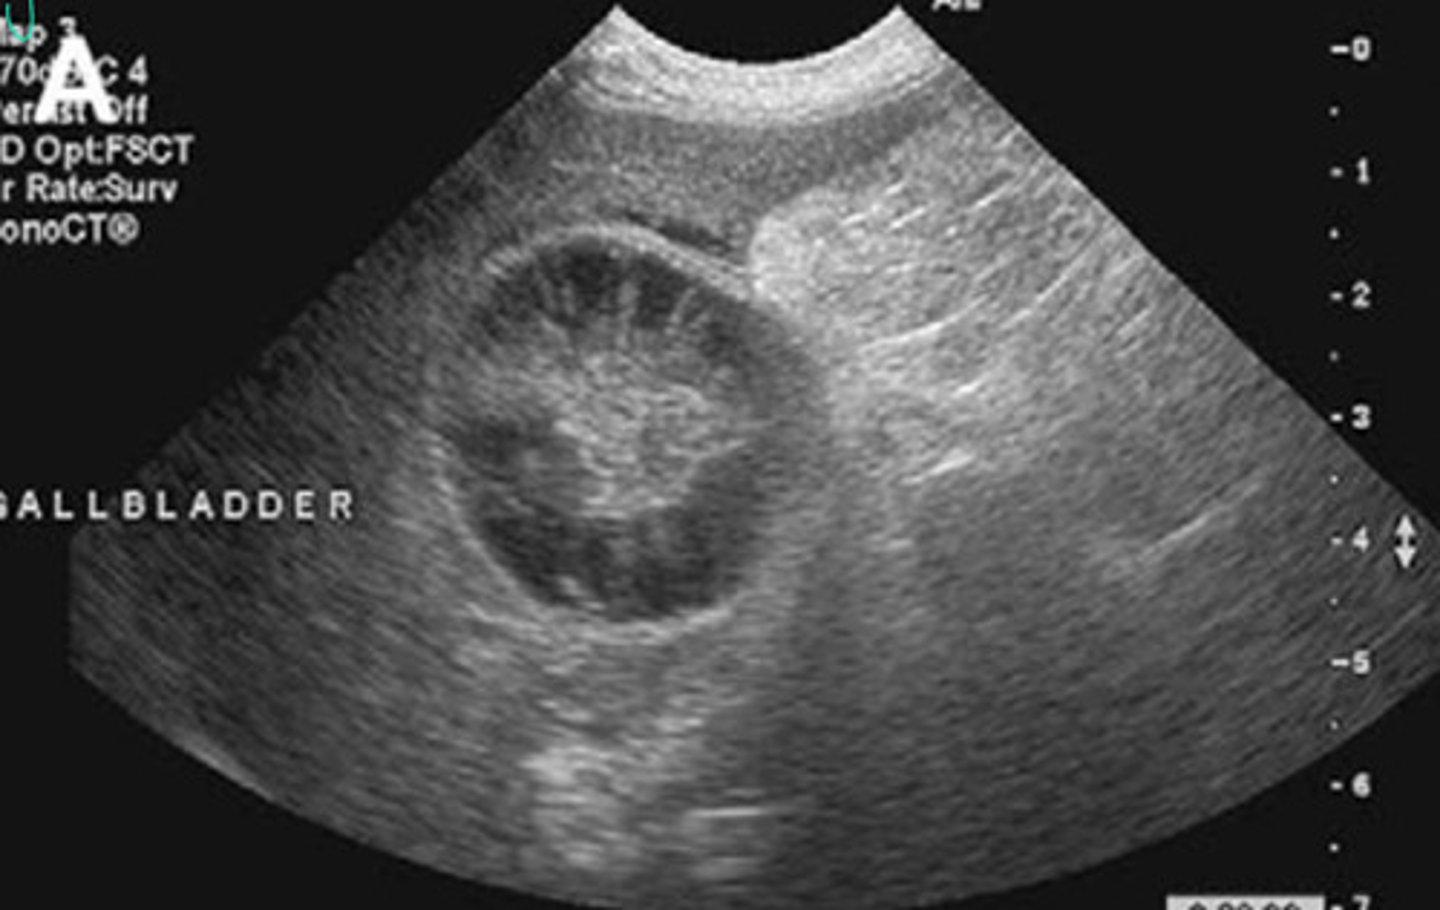

Abnormal = mucocele in the gallbladder

What is going on here? Is this normal or abnormal?